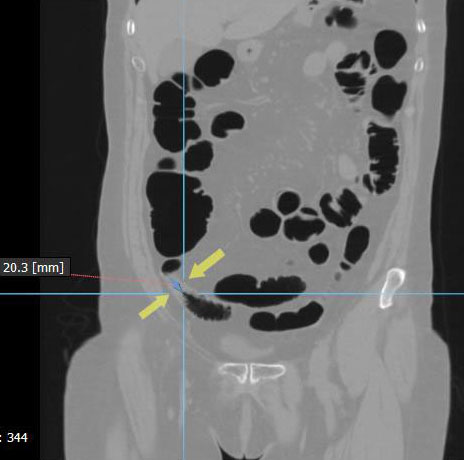

Циркулярный рак тонкой (подвздошной кишки)

Необходимо отметить, что данная патология довольно редко встречается, как правило выявляется на операционном столе у пациентов с тонкокишечной непроходимостью. На данном примере демонстрируем, что дефект кишки был диагностирован на основании 3D реконструкции, а затем уже целенаправленно подтвержден сканограммами с протяженностью процесса и степенью сужения кишечной трубки. Сыграла свою роль сопутствующая патология, которая имела место быть, а именно слабость Баугиниевой заслонки, за счёт чего тонкий кишечник полностью заполнился газом, хотя целью исследования было исключить патологию толстого кишечника.

Просвет тонкой кишки до и после дефекта в 3D-эндоскопе